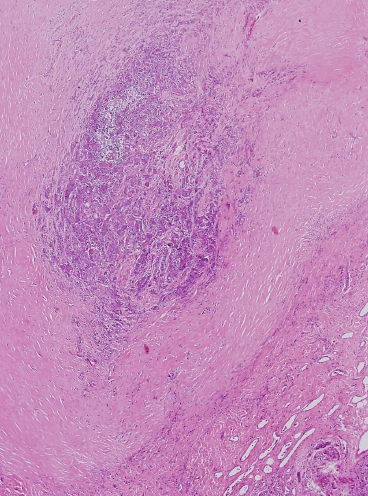

Subacute (de Quervain) granulomatous thyroiditis

Morphology

Histology